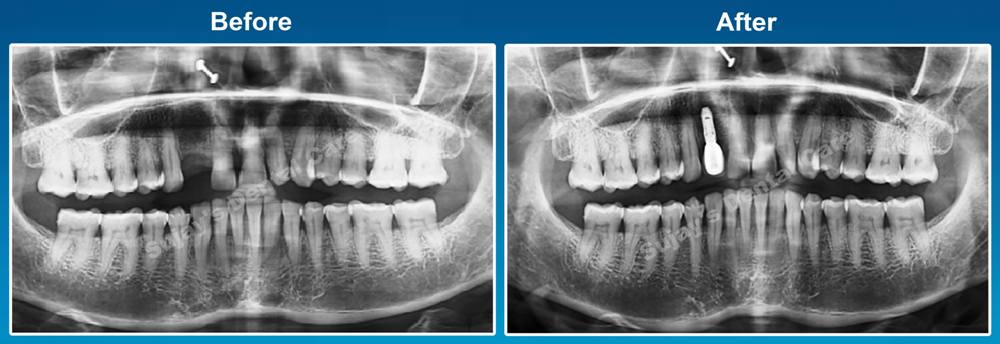

1. رادیوگرافی پانورامیک یا OPG

(Panoramic X-ray)

- تعریف: رادیوگرافی OPG یک تصویر دو بعدی است که نمایی کلی از فک، دندانها و ساختارهای اطراف را نشان میدهد.

- مزایا:

- امکان مشاهده وضعیت کلی فک و دندانها

- شناسایی عفونتها یا مشکلات در لثه و استخوان

- تعیین موقعیت دندانهای باقیمانده و تحلیل فاصلهها

- کاربرد: این نوع تصویر به دندانپزشک کمک میکند تا یک دید کلی از آناتومی دهان بیمار داشته باشد و نقاط قوت و ضعف را شناسایی کند.